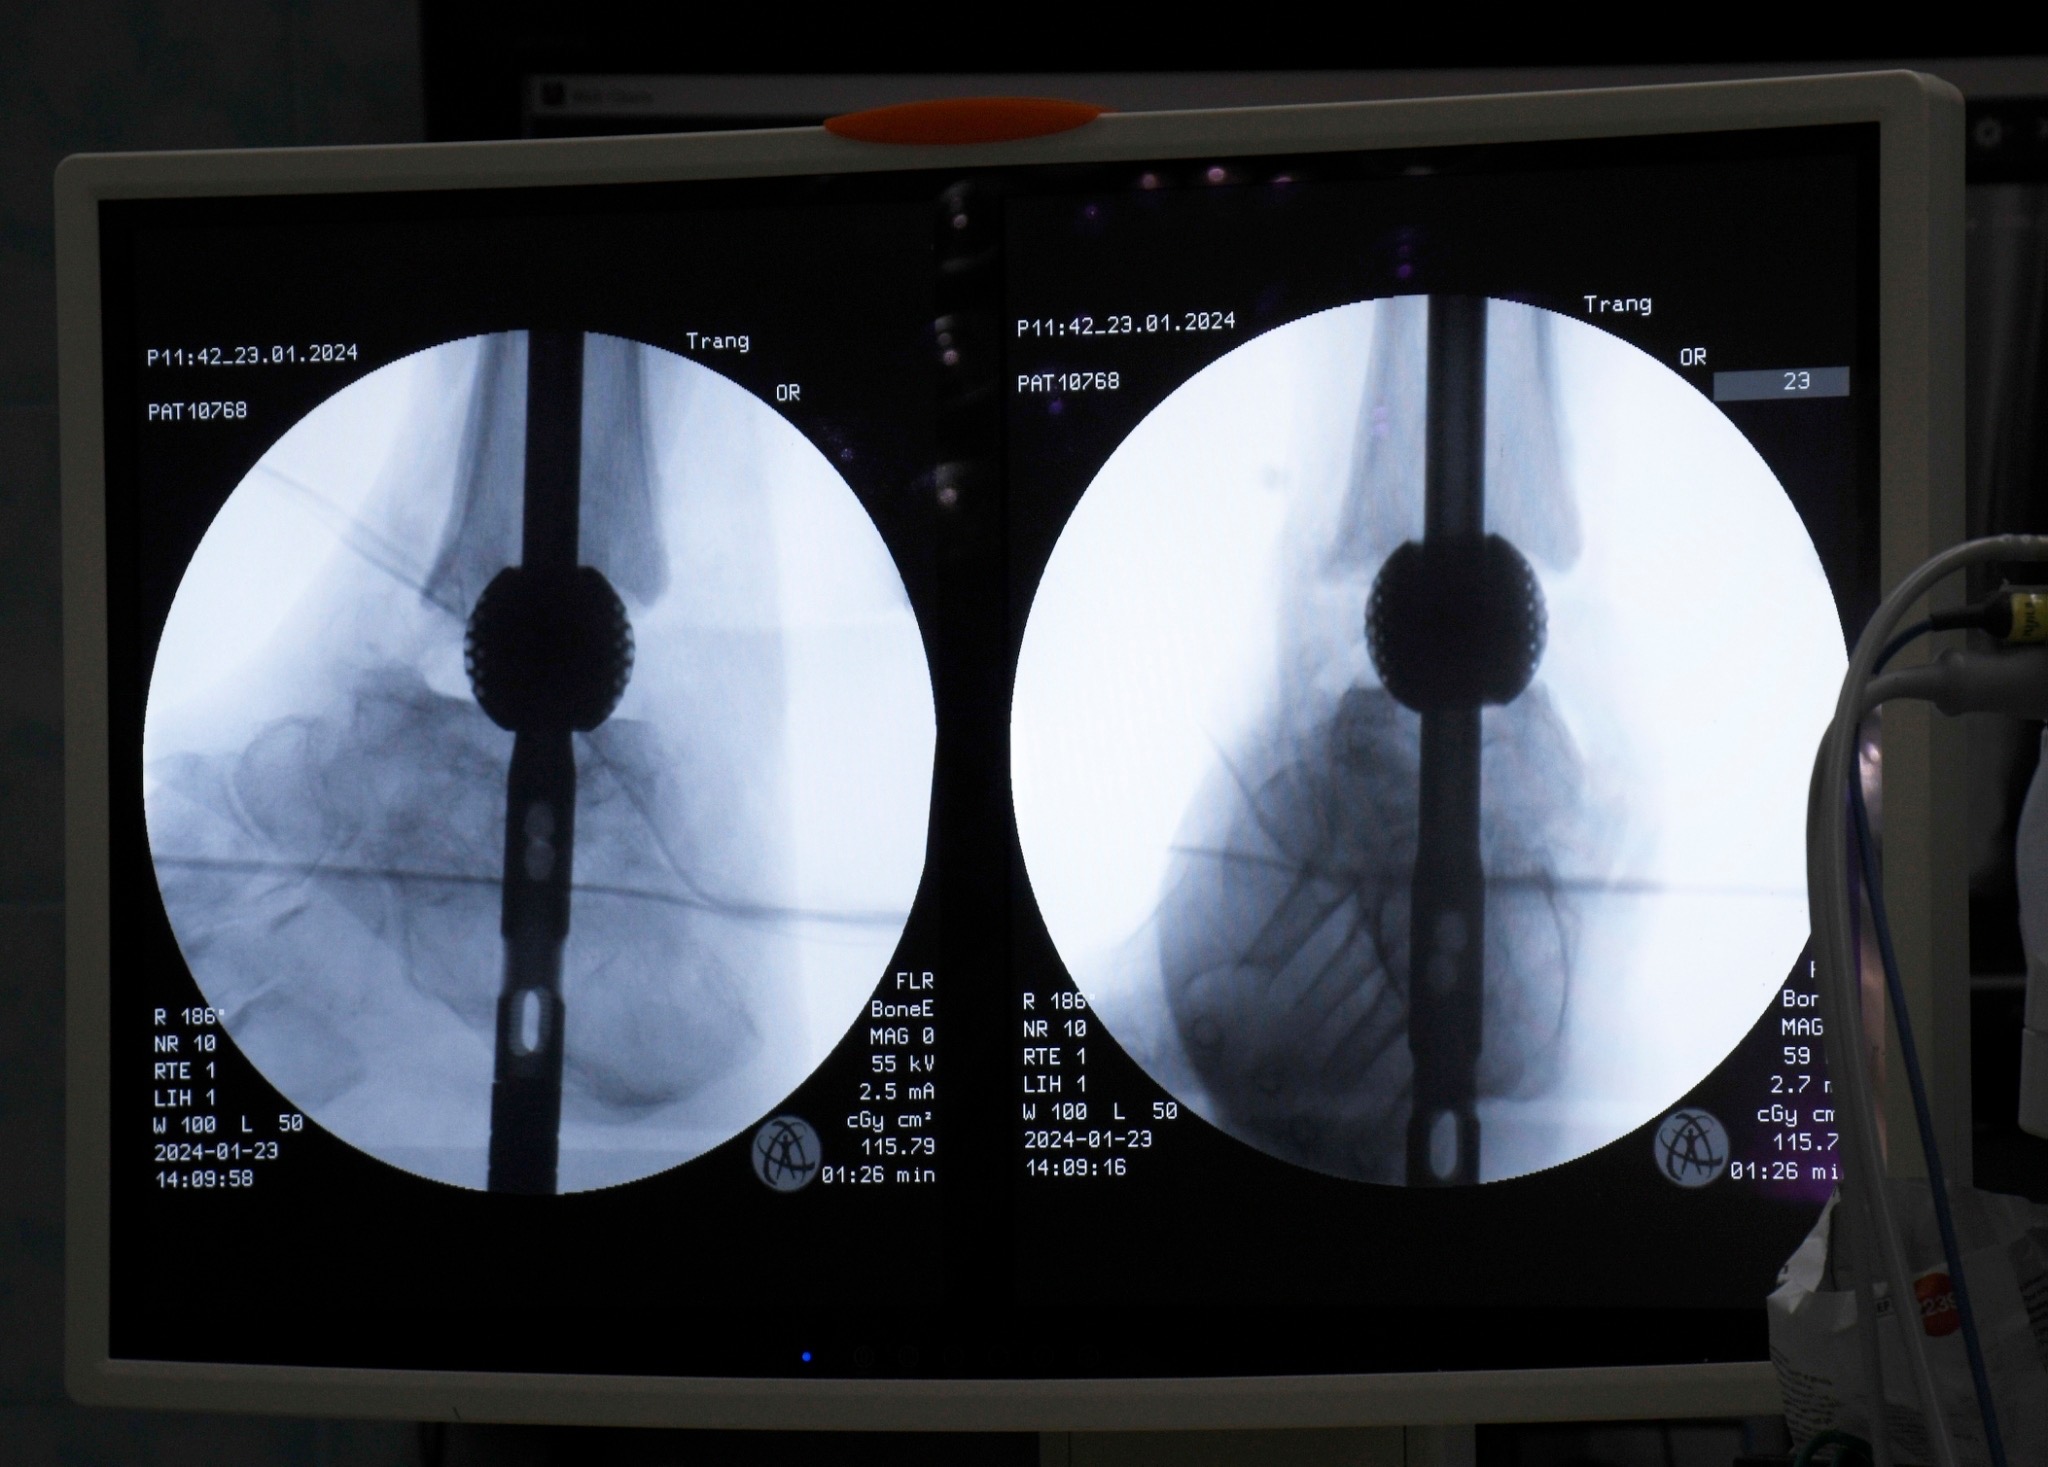

รองศาสตราจารย์ ดร.พชรพิชญ์ กล่าวว่า เทคโนโลยีนี้โดดเด่นด้วยการออกแบบเฉพาะบุคคล ความสามารถในการผสานร่วมกับกระดูกตามธรรมชาติได้ดี และลดความเสี่ยงของการติดเชื้อซ้ำได้อย่างมีนัยสำคัญ ซึ่งนำไปสู่คุณภาพชีวิตที่ดีขึ้นของผู้ป่วย ผลงานวิจัยนี้สะท้อนให้เห็นถึงความสำเร็จทางการแพทย์ในเคสที่มีความท้าทายสูง อาทิ ผู้ป่วยข้อเท้าเสื่อมที่มีภาวะกระดูกติดเชื้อจากโรงพยาบาลตรัง และผู้ป่วยกระดูกหักที่กระดูกไม่ติดกันจากอุบัติเหตุในโรงพยาบาลสงขลานครินทร์ ซึ่งทั้งหมดประสบความสำเร็จในการรักษา ผู้ป่วยสามารถกลับมาเดินได้ตามปกติ แสดงให้เห็นว่าวัสดุหรืออุปกรณ์ที่พัฒนาขึ้นนี้มีความสามารถในการปรับใช้กับกระดูกได้หลากหลายชิ้นทั่วร่างกาย ตอกย้ำถึงความอเนกประสงค์ของเทคโนโลยี

รองศาสตราจารย์ ดร.พชรพิชญ์ เล่าว่า จากแนวคิดที่เริ่มต้นเป็นเพียงงานวิจัยขั้นพื้นฐานเมื่อกว่า 2 ปีก่อน ที่ทีมวิจัยเชื่อว่าน่าจะสามารถต่อยอดไปสู่อุปกรณ์ทางการแพทย์ได้ ปัจจุบันได้พัฒนาและนำไปใช้จริงกับผู้ป่วยแล้ว ทั้งจากการติดต่อโดยตรงของผู้ป่วยและจากการส่งต่อโดยแพทย์เจ้าของไข้ ตัวอย่างเช่น กลุ่มผู้ป่วยข้อเท้าเสื่อมที่มีภาวะกระดูกติดเชื้อจากโรงพยาบาลตรัง จำนวน 7 ราย ซึ่งนำเทคโนโลยีโครงสร้างวัสดุพรุนจาก 3D Printing มาช่วยแพทย์ในการผ่าตัดรักษา ผลลัพธ์พบว่า ภายใน 1 ปี ผู้ป่วยสามารถกลับมาเดินได้ตามปกติทุกคน จากเดิมที่ผู้ป่วยบางรายมีความเสี่ยงต้องถูกตัดขาและไม่สามารถใช้ชีวิตได้อย่างปกติ นวัตกรรมนี้ช่วยเปลี่ยนคุณภาพชีวิตของพวกเขาไปอย่างสิ้นเชิง ความสำเร็จดังกล่าวยังนำไปสู่การยื่นจดสิทธิบัตรในประเทศสหรัฐอเมริกา ร่วมกับ นายแพทย์จรวด จำปา อาจารย์แพทย์โรงพยาบาลตรัง เพื่อขยายการใช้งานอุปกรณ์สู่ระดับนานาชาติ โดยเฉพาะอย่างยิ่งกับโรคเบาหวานที่ถือเป็นปัญหาสาธารณสุขสำคัญทั่วโลก